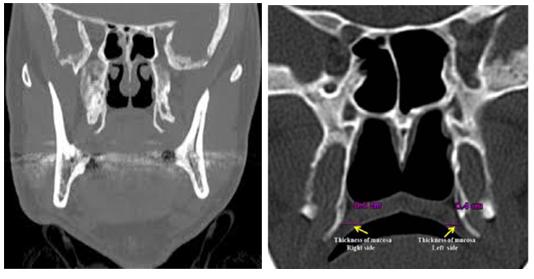

翼钩综合征是因翼钩退行性变或翼钩增生过长引起上颌、耳咽及头部等部位疼痛,切除翼钩后疼痛等症状消失的一种头面疼痛症候群,并合并其他神经*能官**症状,如气促、头痛甚至颈肋区放射性疼痛等。

翼钩是在口腔上腭两侧的蝶骨翼内板的小突起,为腭帆张肌勾绕。正常人一般突起不明显,如果长期腭帆张肌紧张,致使翼钩发生退行性病变,刺激咽舌部神经等引起疼痛;或由于翼钩过长和滑囊炎症引起相应部位疼痛。

本病一般多为单侧发病,阵发性或持续性腭咽部疼痛,吞咽时诱发或加重,部分患者或伴有咽喉异物感或不适,颞颈部酸痛或不适。在局部可见明显的突起或触压痛,这种疾病没有经验的医师往往被误诊为慢性咽炎等,所以很多患者常反复多次就医,或以咽喉炎长期治疗而不见效果。

因此,该病应与舌咽神经痛、茎突综合症、咽喉局部的炎症等相鉴别。首选手术治疗,次选局部封闭治疗。经过手术治疗的翼钩过长患者大多可以获得明显的疗效,很少复发。一般预后良好。